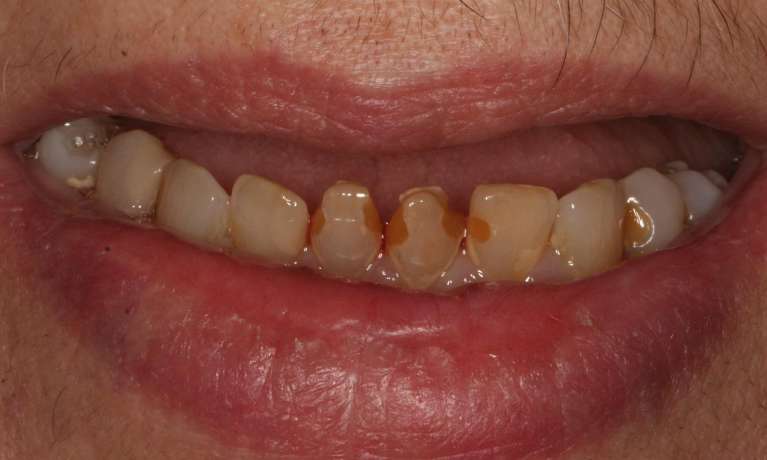

A young teenage with gaps, missing teeth and heavily decayed teeth came to our practice. The whole procedure started with restoring his teeth, 2 years of braces, and and then finally crowns in his early 20s to create the finished smile. His new smile will be maintained with regular dental cleanings and maintenance.